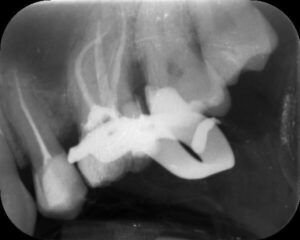

- Diagnostyka – RTG lub tomografia CBCT pozwala ocenić liczbę kanałów i obecność zmian zapalnych.

- Korona protetyczna – przy dużych ubytkach, trwałość na lata,

- Most protetyczny – gdy konieczna jest szersza odbudowa funkcji zgryzu.

Leczenie kanałowe to skuteczna i bezpieczna metoda ratowania zębów. Dzięki nowoczesnym technologiom w Centrodencie możliwe jest uratowanie nawet bardzo zniszczonych zębów, które później mogą pełnić rolę filarów pod korony i mosty protetyczne.